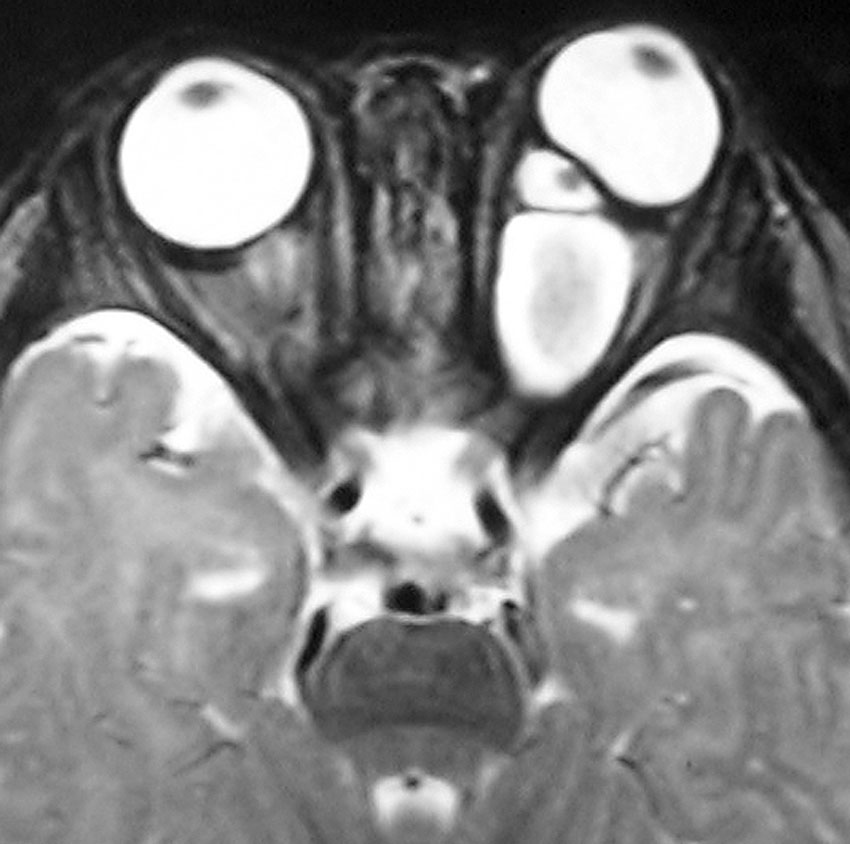

whole optic pathway pilocytic astrocytomaとは

両側の眼窩内視神経から視交叉、視索,外側膝状体,内包後脚,視放線近位部までが腫瘍化しています。FLAIRで高信号で,不規則にガドリニウム増強されます。これを手術摘出したり生検したりしても無駄です。放射線治療は不可能であり治療方法は化学療法のみです。

この子はCDDP/VCRの化学療法から開始して12年になりますが,今は無治療でわずかな視力ですが学校に通っています。優等生です。自然退縮を見ていますが,今後も変化する可能性はすこし残しています。